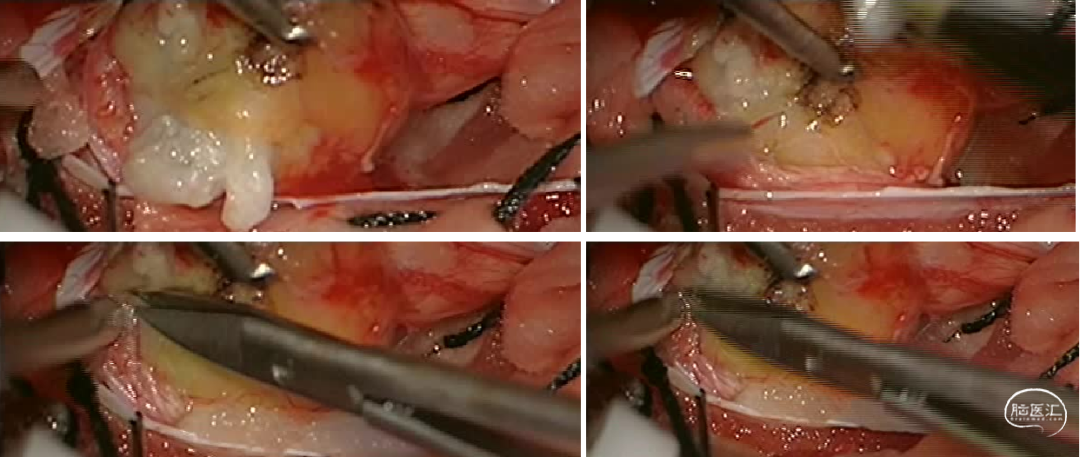

陈卓鹏医师在内镜和显微镜中的协助为手术的顺利完成提供了帮助。肿瘤挤压脊髓圆锥,与其及马尾神经根粘连紧密,显微下切除视野直视下肿瘤,内镜辅助下予以切除肿瘤两端,马尾神经根完好保留,内镜下操作直视外部分肿瘤,减少对神经根的牵拉,降低了术后患者不适发生的机率。术后患者腰部下疼痛及肢体活动障碍症状明显改善。